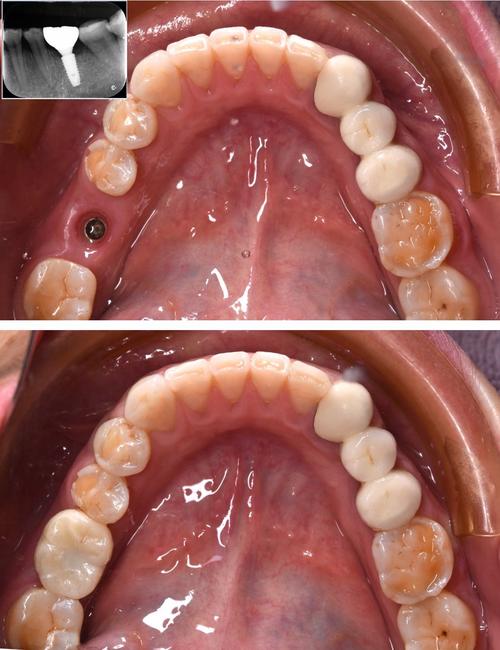

术后当天,伤口可能会有轻微肿胀或疼痛,医生会开止痛药和消炎药来缓解;术后24小时内不能刷牙漱口,以免血块脱落,之后可以用温盐水轻轻漱口;饮食上要吃温凉的软食,避免过硬、过热的食物刺激伤口,植骨后3-6个月,新骨会逐渐形成,与自体骨长在一起,此时再通过二次手术切开牙龈,安装种植体,完成种牙的“第二步”。